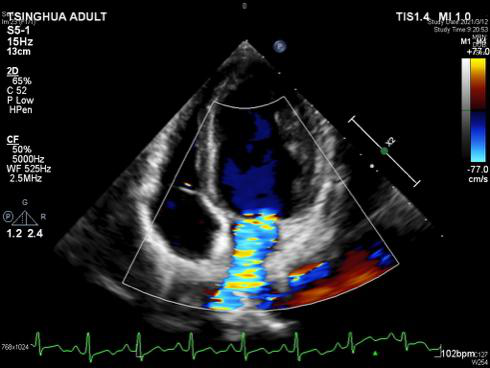

图一   心脏超声显示二尖瓣大量反流                                   图二 左侧腘动脉以下闭塞

通常这种情况下想保住二尖瓣很难,本可以按照计划将二尖瓣换成机械瓣,但考虑以后孩子要长期服药,还有面临二次手术风险的可能。“我们还是尽量让他使用自己的瓣膜,不要给孩子留下遗憾!”这样的信念使得崔晓征毫不犹豫地再次打开洋洋的心脏,对二尖瓣进行了二次修复。心脏再次复跳后,超声显示瓣膜干干净净,反流几乎完全消失,洋洋的二尖瓣保住了!。